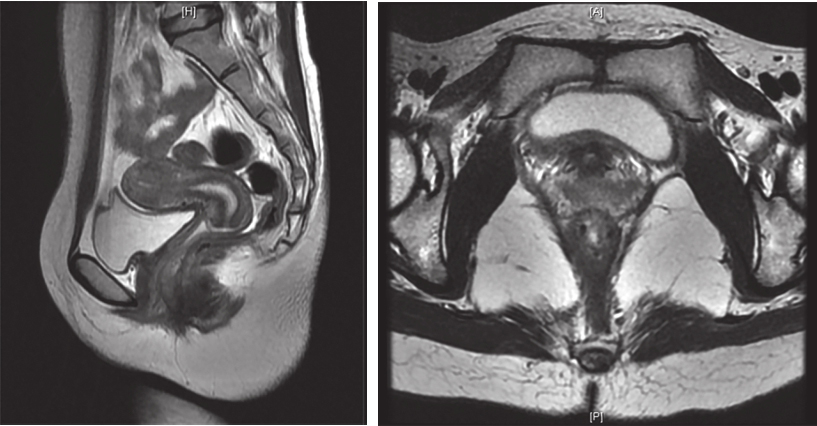

患者,女性,33岁,于2016年4月8日因“发现会阴部肿物1年半”就诊。患者于2014年10月体检发现“左侧阴道内壁囊肿”,无疼痛,无接触性出血,未行治疗。2015年10月时感觉经期阴道左侧坠胀感,行超声检查考虑“左侧前庭大腺囊肿”,予中药治疗,效果不佳。2015年11月自觉肿物增大、向外膨出,伴尿细、排尿不尽感,未见异常分泌物,行妇科超声检查示:阴道壁外口左侧见一囊实性结构,大小约2.3cm×2.1cm×2.3cm,边界清楚,内透声差,可见密集点状回声。2016年2月自觉肿物增大伴疼痛、会阴区红肿,于外院以“前庭大腺囊肿伴感染”收住院,并行抗感染治疗,自觉症状稍缓解。2016年3月于外院行前庭大腺囊肿切除术,术中发现囊实性肿物,以实性成分为主,考虑肿物性质不明确,遂暂停切除术,行囊性成分穿刺吸取血性液体3ml,送细菌培养阴性。术后持续有血性渗出,自觉肿物变大,行抗感染治疗后疼痛稍缓解。行超声引导下经会阴穿刺活检术,病理示:梭形细胞肿瘤,细胞中度异型,核分裂象易见(18 个 /50 HPF),免疫组织化学染色:CD117(+),CD34(+),S-100(-),Ki-67(Li:10%~20%),ER(-),PR(-),考虑胃肠间质瘤(高危)可能性大。穿刺组织基因检测:c-KIT基因11外显子缺失突变(c.1670-1675delGGAAGG.)。术后患者自觉肿块明显增大,疼痛加重。完善盆腔MRI(图1):直肠下段与阴道间见类椭圆形混杂软组织信号影,最大截面约5.7cm×3.7cm,增强扫描见不均匀强化,病变与直肠前壁、阴道后壁均分界不清,邻近组织受压移位;阴道上段梗阻积液。

图1 首诊盆腔MRI表现

引自:胃肠间质瘤典型病例诊治与解析.第1版.ISBN:978-7-117-30146-6.主编:陶凯雄 曹 晖

盆腔MRI(图5):直肠下段与阴道间GIST,与阴道后壁及直肠前壁分界不清,大小约为3.3cm×2.1cm×1.7cm,与前片比较无显著变化,DWI未见明显高信号,增强扫描未见明显强化。盆腔存在少量积液。

A

B

图5 术前盆腔MRI表现